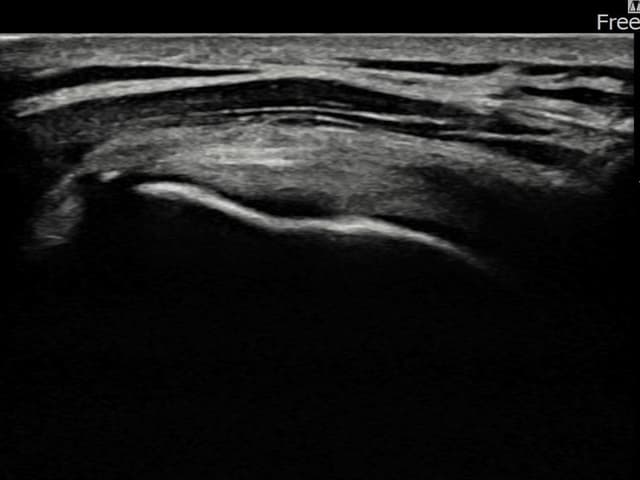

左侧 冈上肌腱 石灰化肌腱炎

9mm × 7mm